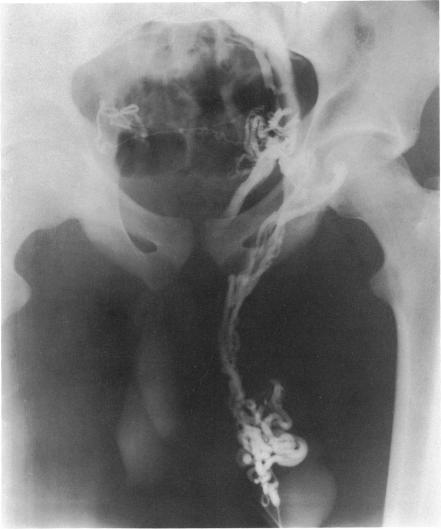

Changes in the appearance of venography after ligation of a varicocele.